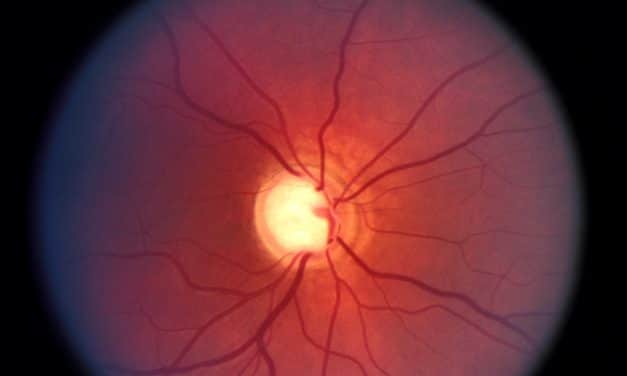

Per saperne di piùIntegratori per ridurre la pressione oculare e per il glaucoma La pressione oculare è...

Per saperne di piùPressione oculare e glaucoma La pressione oculare è l’indice più importante predittivo per...